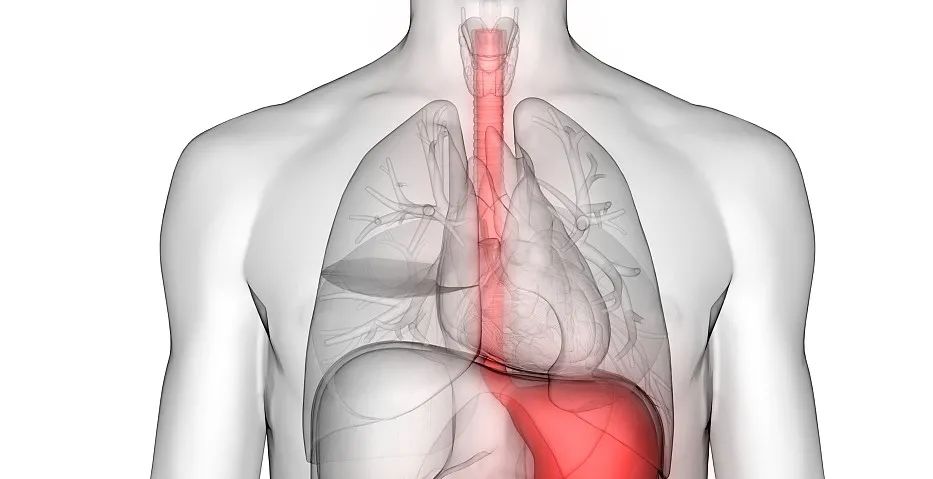

(上圖:增強CT食管壁不規則增厚)

CT表現:

①食管壁改變:食管壁全周環形或局部不規則增厚,相應平面管腔變窄或消失,呈腫塊樣改變;

②食管周圍脂肪間隙模糊、消失:提示食管癌向外侵犯;

③周圍組織器官受累:多為氣管和支氣管,常形成食管-氣管瘺,其次可侵犯心包膜、左心房和主動脈等;

④轉移:以縱隔、肺門及頸部淋巴結轉移多見,也可逆行性轉移至上腹部淋巴結,少見肺轉移。CT增強掃描可見瘤體輕度強化。較大瘤體呈不均勻強化,常合并低密度的壞死灶,較小瘤體強化均勻。

下段食管癌CT圖像

下段食管腔消失,呈腫塊樣改變,平掃呈等密度,增強后有明顯強化